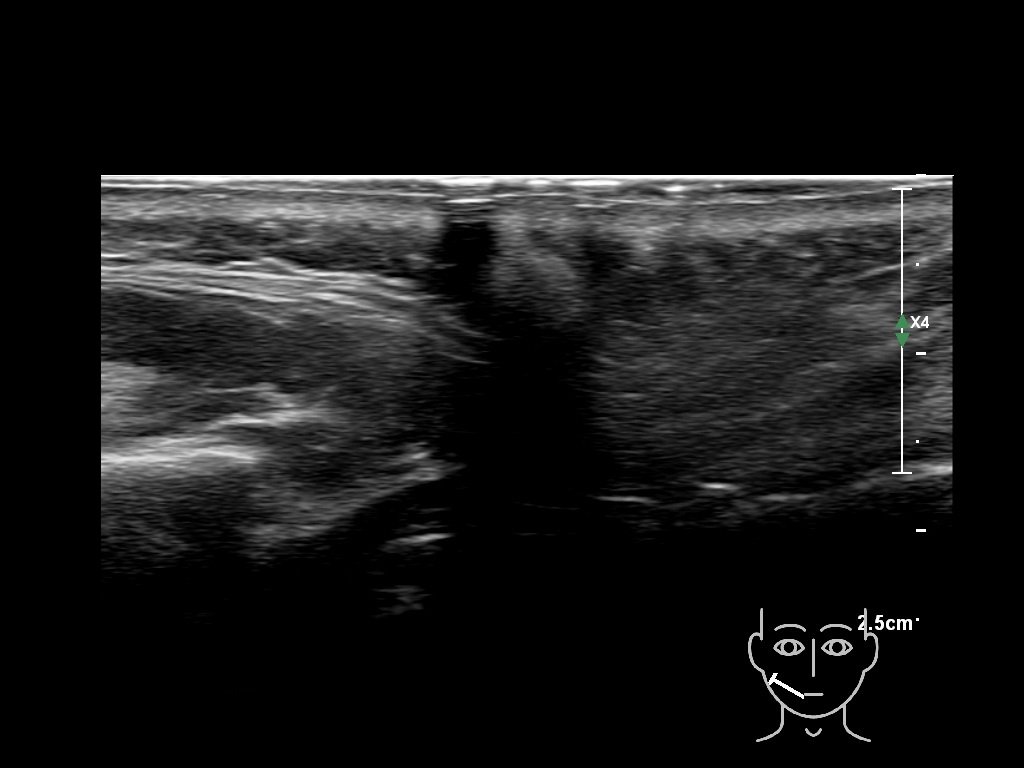

Draw in the image on the right where the fillers are located. To check if your answer is correct, please click on the secondary image.

Fillers

Draw in the second image below where the fillers are located. To check if your answer is correct, swipe the first image to the right.